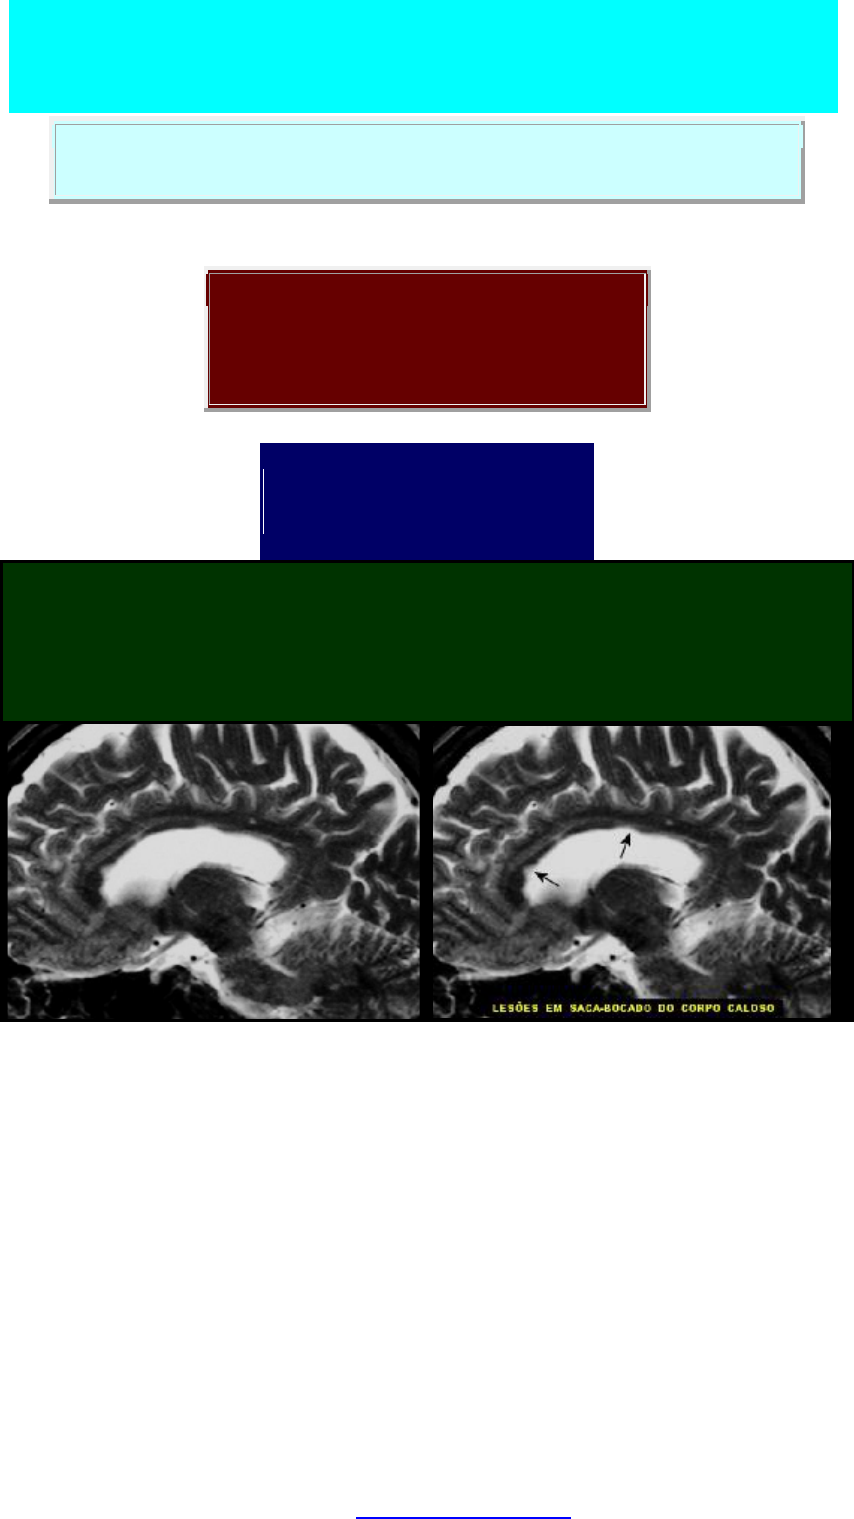

CORTES SAGITAIS, T2. Este caso presta-se bem a demonstração

das lesões características da esclerose múltipla no corpo caloso e coroa

radiada. No corpo caloso, há afinamento da comissura e lesões

desemielinizantes em saca-bocado na face inferior. Um pouco

lateralmente, à D ou E, observam-se lesões na coroa radiada, baseadas no

ângulo súpero-lateral do ventrículo, e que imitam chamas ou labaredas.

LESÕES EM CORPO CALOSO, T2. Bandas de desmielinização de

espessura irregular alternam-se com mielina preservada nestes cortes

parasagitais pelo corpo caloso. Em ambos, há também hipersinal na ponte,

maior na foto à E.